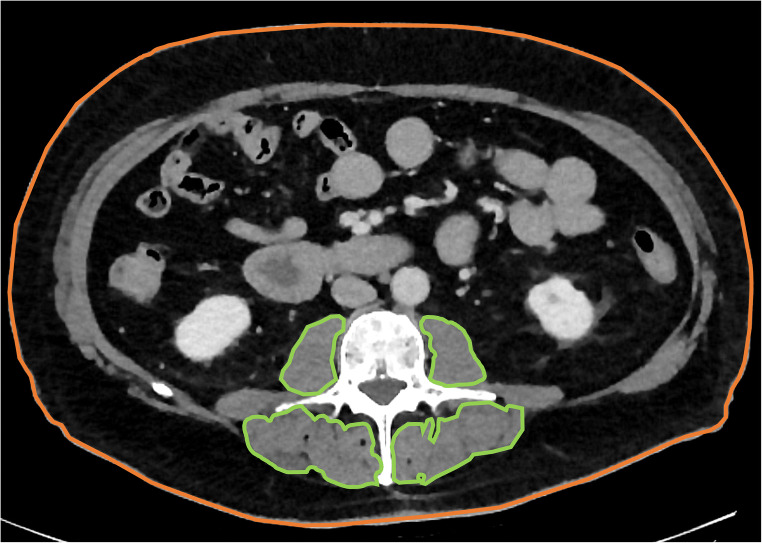

The abdominal measurements were carried out at the height of L3 in accordance with earlier, well-established methods: A sagittal plane was used to identify L3, and all measurements were then performed on an axial plane located centrally at this height. The area of the following regions was recorded: psoas major muscles, autochthonous spine muscles, and total cross-sectional area of the patient’s body. The combined total of all individual muscle areas was defined as the total abdominal paraspinal muscle area (see Fig. 1).

Fig. 1.

Overview of the abdominal 2D measurements. Measurements of muscle (outlined in green) and the total cross-sectional area (outlined in orange) were performed using a freehand ROI tool within the standard PACS at the height of the third lumbar vertebra